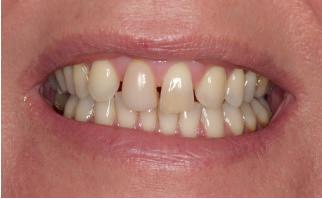

1. Studiofoto intake

aan zijn gebit gedaan behalve pappen en nathouden. Tandheelkundige zorg werd enkel verleend wanneer er zich een probleem voordeed (afbeelding 1, 3, 5).

Ook de rol van de patiënt is hierin van doorslaggevend belang. In dit geval toonde de patiënt een hoge mate van motivatie en betrokkenheid. Hij verbeterde zijn mondhygiëne aanzienlijk en bleef gedurende het gehele behandeltraject therapietrouw en besluitvaardig. Zonder deze actieve medewerking was het bereikte resultaat niet mogelijk geweest. Het eindresultaat leidde tot merkbare tevredenheid bij de patiënt, die na afronding van de behandeling aangaf zich zichtbaar en voelbaar tien jaar jonger

te voelen (afbeelding 18) Een uitspraak die treffend weerspiegelt wat bereikt kan worden wanneer visie, interdisciplinaire samenwerking en patiëntbetrokkenheid samenkomen.